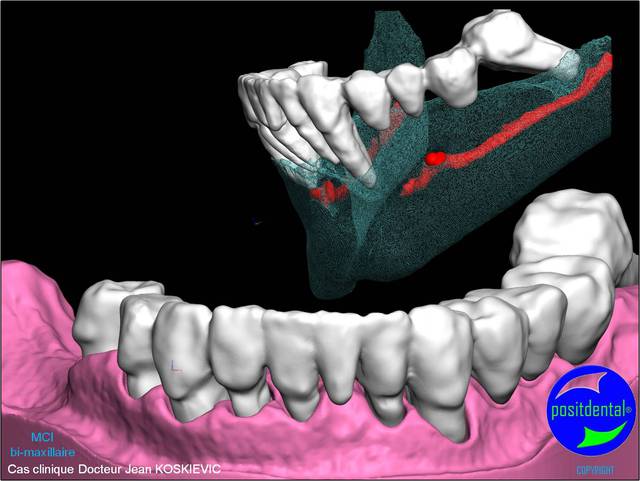

Montage esthétique ou wax-up 3D

S.I.A.O.

Mci - Eugenol